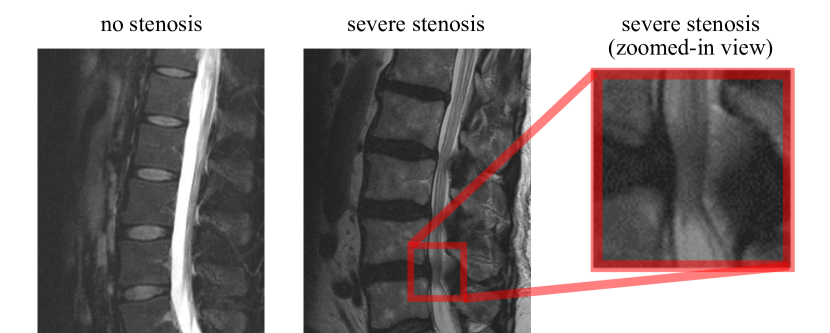

Refer to caption

Figure 3: Example of a case without lumbar spinal stenosis and with severe lumbar spinal stenosis.

For each MRI exam, the associated radiology report was automatically parsed for keywords indicative of the presence and severity of stenosis for each of the 6 vertebral disc levels (T12-L1 through L5-S1) to extract ground truth labels for a total of 6,093 gradings. Each grading was assigned to a value on a four-point ordinal scale of stenosis severity: 0 (no stenosis), 1 (mild stenosis), 2 (moderate stenosis), and 3 (severe stenosis). Examples of patients with and without stenosis are shown in Figure 3.